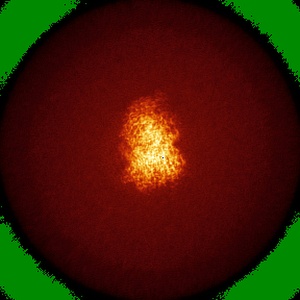

Human Amylin1 Receptor in complex with Gs and cagrilintide

Single-particle2.2 Å

Sample: Human Amylin1 Receptor in complex with Gs and cagrilintide

Structural and dynamic features of cagrilintide binding to calcitonin and amylin receptors.